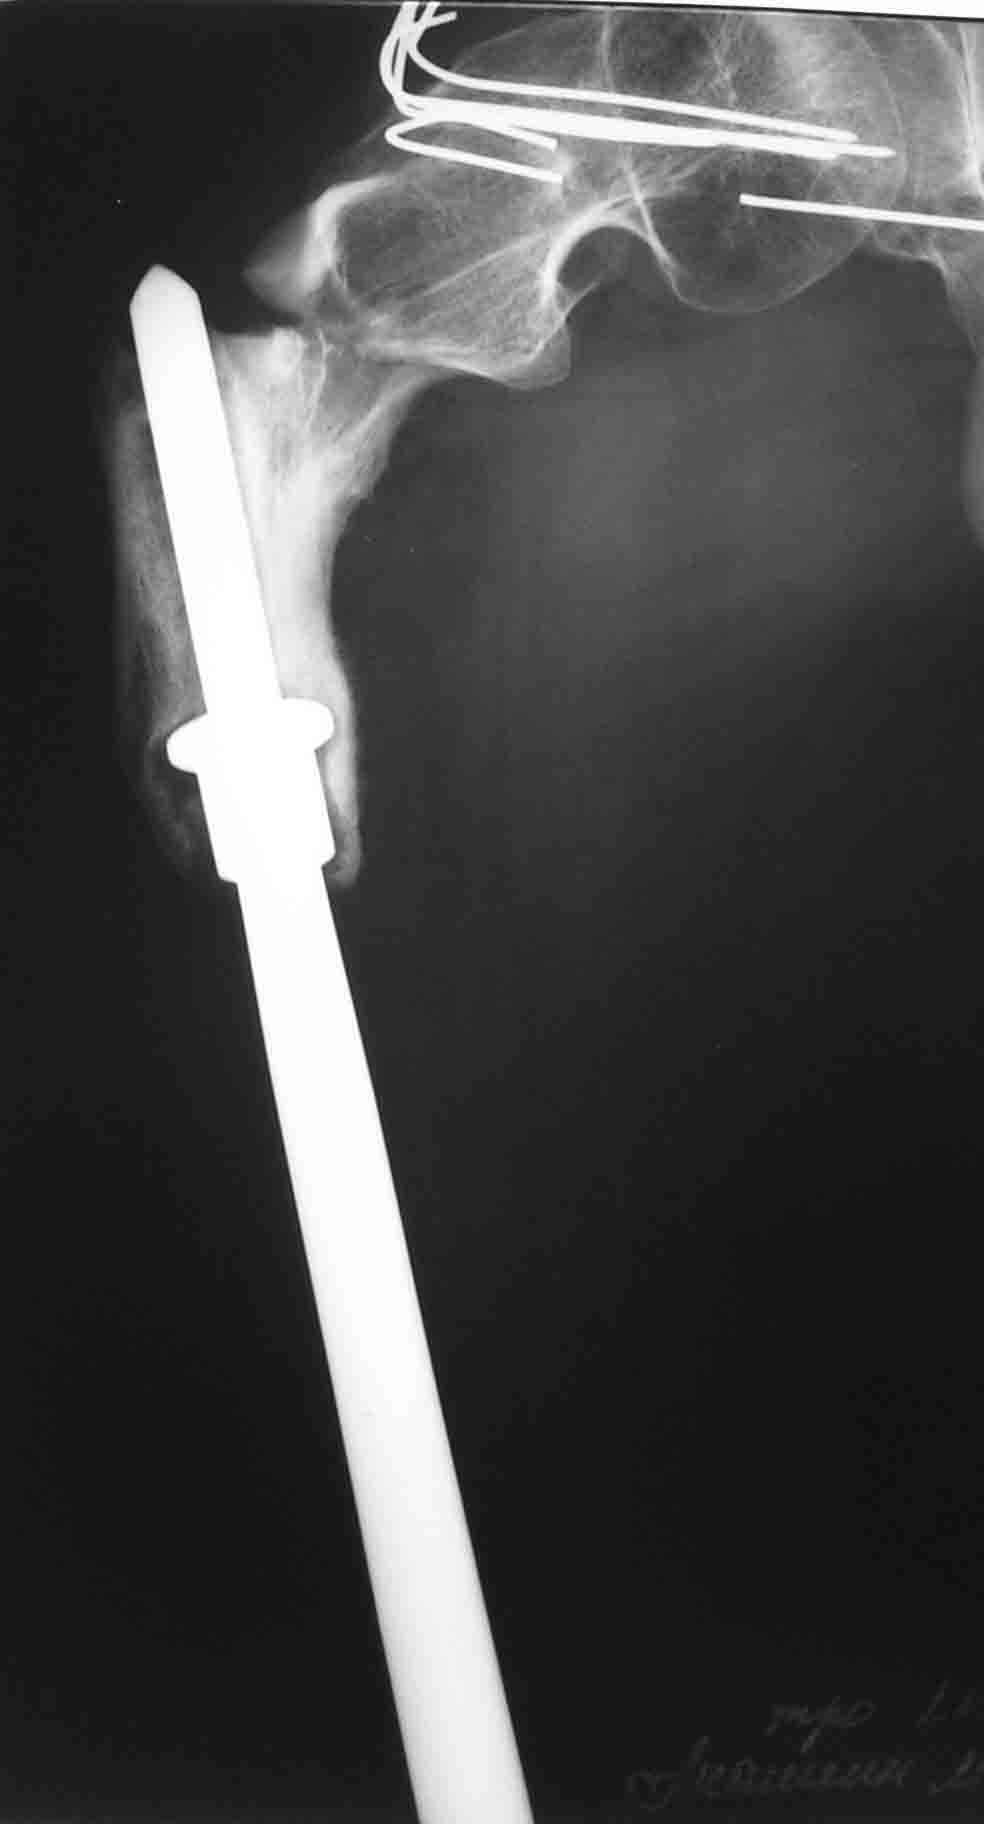

Пациент находится в Вологде. Это 500 км к северу от Москвы.

До травмы передвигался самостоятельно с дополнительной опорой (трость). Имеется укорочение ноги 15 см.